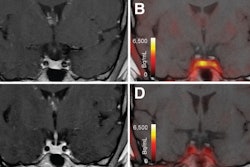

Group mean C-11 PBR28 SUVR maps of females with ASD (top) and female controls (middle). Statistical map from voxelwise comparison of C-11 PBR28 SUVR between groups, controlled for age and TSPO genotype, shows elevated regional TSPO levels relative to whole brain mean in the midcingulate cortex and splenium of the corpus callosum in ASD (N = 12) compared with controls (N = 10) (Z > 2.3, pcluster) (bottom). TSPO =

translocator protein, ASD = autism spectrum disorder, CON = control, SUVR = standardized uptake value ratio, N = number. Image and caption courtesy of Neuropsychopharmacology.

The scans showed that women with ASD exhibited elevated C-11 PBR28 standardized uptake value ratios (SUVRs) in the midcingulate cortex and splenium of the corpus callosum compared to healthy controls. In addition, no brain area showed lower C-11 PBR28 SUVR in females with ASD compared with participants without ASD, according to the findings.